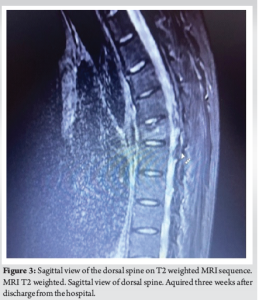

We report the case of a 44-year-old Caucasian male patient (187 cm height, 78 kg weight) without any significant medical history presented to the Emergency Department complaining about palpitations and dyspnea. Electrocardiography showed the presence of high-rate AF without hemodynamic impairment. Blood examinations were performed at admission: aspartate and alanine aminotransferase, creatine, bilirubin, potassium, sodium, amylase, lipase, C reactive protein, leukocytes, hemoglobin, and platelet levels were within limits (Table 1). An initial rate control approach with beta intravenous metoprolol was performed and the patient was admitted to the Cardiology Department. He underwent transthoracic and transesophageal echocardiography that excluded the presence of major cardiac structural abnormalities or intracavitary thrombosis. Thereafter, the cardiologist planned and performed an ECV by use of a single biphasic 100 J direct current (DC) shock with anteroposterior leads position after appropriate sedation (intravenous five mg midazolam bolus). The patient complained of acute back pain just after the first cardioversion procedure. Pain was partially responsive to standard painkillers and worsened in standing position with partial bilateral thoracic irradiation. Regarding the pain progression, the patient began experiencing rachialgia immediately after recovery from anesthesia on the day of the first procedure; this pain persisted and worsened following the second and third cardioversions, which were associated with two cardiac ablations performed in the following days. The patient was discharged from the hospital after the third cardioversion with complete resolution of the AF and no evidence of procedure-related complications. Persisting the dorsal pain after hospital discharge, the general practitioner prescribed a magnetic resonance imaging (MRI) of the painful thoracic spine. Three weeks after discharge, MRI revealed a T6 (sixth thoracic) vertebral body fracture (Fig. 1-3). Given the timing between the cardioversion procedure and the onset of pain, the fracture was considered a post-cardioversion procedure complication. It was a wedge-shaped fracture with superior endplate major involvement and bone edema. No posterior vertebral body wall interruption occurred and the patient was completely free from neurological symptoms. Treatment with bisphosphonates and cholecalciferol supplements was initiated. After 3 months of conservative treatment, the pain disappeared, leaving a temporary residual paravertebral muscular contracture. The patient is a non-smoker with no bone disorders, aside from slight osteopenia observed in computerized bone mineralometry, and no previous history of spine fractures or back pain. He was not on any medication before AF. His past medical history includes fractures from significant trauma (nasal septum, cheekbone, third finger of the hand) and cervical radiculopathy 20 years ago, which had resolved. Furthermore, he has previously not experienced any back pain. No falls or trauma were reported during the hospital stay.

The patient of this case report was treated for AF by use of a single biphasic 100 J DC shock and began to experience thoracic rachialgia just after the first cardioversion procedure. After 3 weeks of persisting pain, MRI revealed a T6 vertebral fracture. Since ECV was the only anamnestic feature that could be potentially correlated, we hypothesized an association between the vertebral fracture and a massive muscular contracture induced by the ECV that was performed on the patient three weeks earlier. DC cardioversion shock can be delivered by monophasic or biphasic current. The shock can be synchronized with the peak of the QRS complex (synchronized cardioversion) in case of supraventricular arrhythmias or stable ventricular tachycardia. In case of non-synchronized DC shock, the procedure is defined as electrical defibrillation. Many studies demonstrated that biphasic shock waveforms presented a more favorable efficacy and safety profile compared to monophasic shock [4-6]. ECV can be performed by positioning the electrical pads in anteroposterior or anterolateral position [7,8]. The use of anteroposterior electrode position has been associated with higher rates of successful ECV in the literature [9]. Overall, cardioversion is considered a safe procedure. However, some complications are described and should be explained to the patients through a consent form. Notably, sequelae related to bone injuries or fractures are not taken into account in differential diagnosis in patients presenting with back pain after cardioversion and are not cited in consent forms neither in Italy nor in the United States. The occurrence of a thoracolumbar compression fracture in a cardioverted otherwise healthy patient, with no predisposing factor for bone weakness, is documented in literature in only two complete and accessible case reports described by Koda in 2020 and Wilsmore in 2018. In his case, Koda reported that a single 200 J DC shock was performed with pads placed on anteroposterior sites in order to treat AF with elevated ventricular rate [10]. In the other report, Wilsmore documented the administration of a single biphasic shock during ECV for AF [11]. Cases of vertebral fractures were also reported in a different clinical context that is multiple defibrillations for ventricular tachycardia [12,13]. All these cases involved relatively young patients without any major orthopedic or systemic risk factor for spontaneous bone fractures. Moreover, this rare complication occurs both after monophasic and biphasic shocks and it appears to have no relation with the energy applied during the shock. Few case reports in literature describe fractures involving upper limbs (more common) and lower limbs caused by electrical discharge [14-17]; this mechanism is typical in HV (high voltage) electric shock because more likely to happen [18], although fractures caused by LV (low voltage) are described [19]. In a not therapeutic case report, vertebral fracture has been related to the electric weapon used by police enforcement [20]. Few case reports regarding fractures associated to electric shock exist in literature, although they are not fully accessible [21-23]. Many authors describe the mechanism as a prolonged and uncontrolled contracture of muscles that leads to the compression fracture, mainly in fragile (e.g., children) and osteoporotic patients. Moreover, there is the evidence that tetanic muscle spasm in seizures can cause fractures. Other known complications in seizures or electric shocks are glenohumeral dislocation, even bilateral. The spastic reflex induced by electric energy during cardioversion may account for superior vertebral endplate fracture with anterior wedging and posterior wall integrity, that is the significant finding in Koda’s and Wilsmore’s case reports as well as in our patient. The flexion contracture mechanism acts on the anterior wall of the vertebra; differently from the well-known mechanism of axial compression occurring when the force of impact is vertical along the axis of the spine, as in a fall onto the feet or buttocks. The risk of fracture depends on voltage amplitude and frailty of the patients, nevertheless a low voltage energy can cause fracture in young and healthy patients. Our case and what reported in the literature suggest that a post-procedure X-ray should be considered in all patients with back pain who have undergone a cardioversion procedure. If the X-ray is negative for fracture, an MRI should be prescribed if the patient continues to complain of back pain. Neurological involvement must be ruled out since has been reported in literature, even though extremely rare [10]. Regarding patient’s information, existing the possibility of such complications, it should be taken into account in the informed consent for cardioversion even though extremely rare.